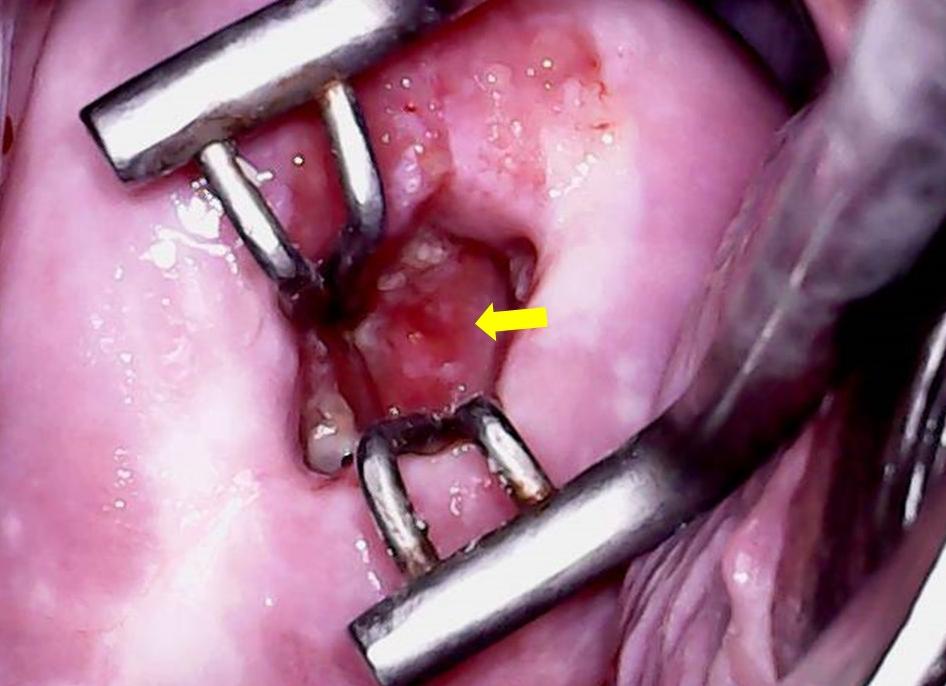

3. Кольпоскопия – наиболее достоверный метод, при котором шейка матки с кистами эндоцервикса исследуется при многократном увеличении.

• Расширенная кольпоскопия. Ткани шейки матки исследуются под микроскопом, что позволяет получить максимально точные сведения об их структуре и возможных изменениях.

На фото слева – цервикальный канал, справа – внешний вид кисты при кольпоскопии.

Большинство кист эндоцервикса являются случайной находкой во время гинекологического обследования: кольпоскопии, УЗИ или томографического обследования.

• видеокольпоскопия – расширенное исследование влагалища и шейки оптическим аппаратом с системой увеличения;

Обязательно осуществляется кольпоскопия. Данный метод особенно показан в том случае, если есть подозрение, что имеется шейка матки с единичными мелкими кистами эндоцервикса.